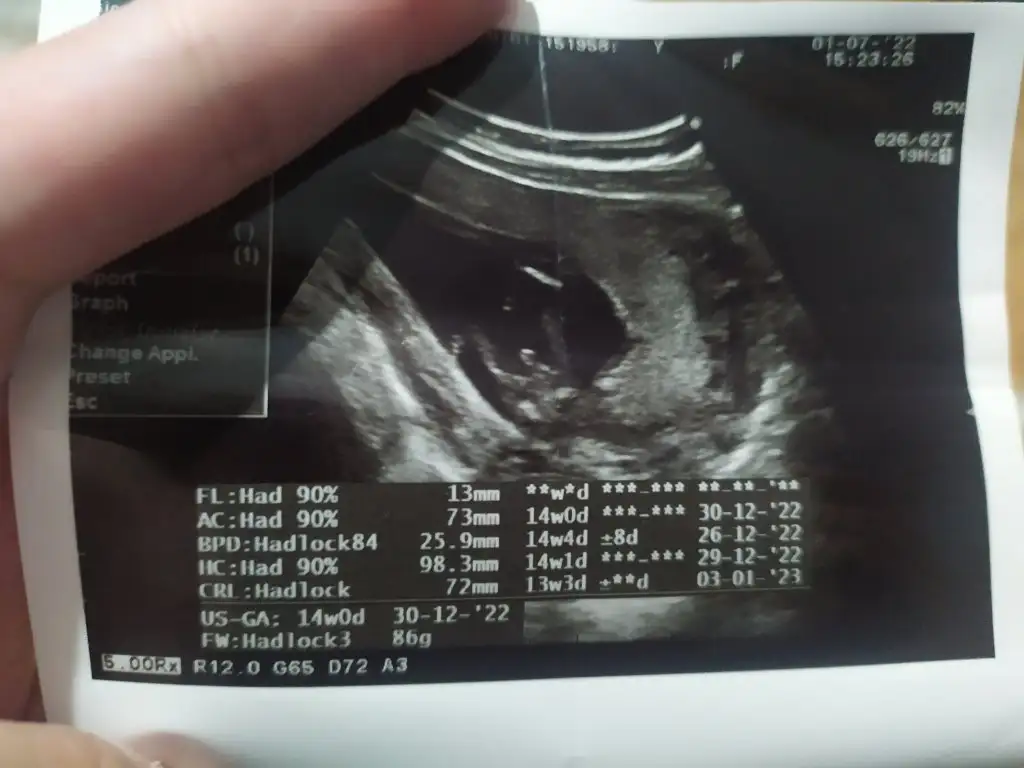

Kız on sekizden önce söylemem dediCanım bence sen 14 de git cinsiyet ne diye sor o zaten dediğini hatirlamiyor. Bakar görürse söyler![]()

Vay arkadaşKız on sekizden önce söylemem dedi![]()

Ya dimi madem söylemiyorsun bari ultrason resmini düzgün ver... Hastanede ki doktora gitsem söyler mi bilmiyorumVay arkadaşsöyle birdahakine güzel resim alsın biz tahmin edelim bari

Bence benim gibi meraklıysan devlete bi uğra cinsiyet icin o adam söylemeyecek gibi baksana kimse tahmin yapmasın diye fotoyu bile fluu yapmış sankiAynen canım saglikli olmaları çok önemli ama insan cinsiyeti de merak ediyor... Bakalım bekleyeceğiz. Bu gidişle doğum da anca öğreneceğim gibi![]()

Flu olsa ona bile razıyım ,Bence benim gibi meraklıysan devlete bi uğra cinsiyet icin o adam söylemeyecek gibi baksana kimse tahmin yapmasın diye fotoyu bile fluu yapmış sanki![]()

Bunu bile geç anladım sizinkinde hiçbir şey göremiyorum13 haftalık kocaman çocuğu bu kadar şahane yakalamayı nasıl başarmış Allahım bu nasıl bir çekimhoş benim de en başta gittiğim bir kese resmi var kese demeye bin şahit aynı adamın bir gün sonra Mehmet bey yusyuvarlak kese çekmişti birde şuna bak ne olur

Bu bacaklar ve pipisi mi yoksa ben mi öyle görüyorumBunu bile geç anladım sizinkinde hiçbir şey göremiyorum![]()

Evet öyleymişBu bacaklar ve pipisi mi yoksa ben mi öyle görüyorum![]()

Ama çok belli .ben normalde pek anlayamam ama burda bariz şov yapmışEvet öyleymiş![]()

Valla bende bir şey anlamıyorum çok çirkin ve anlamsız ultrason resmi olduBunu bile geç anladım sizinkinde hiçbir şey göremiyorum![]()